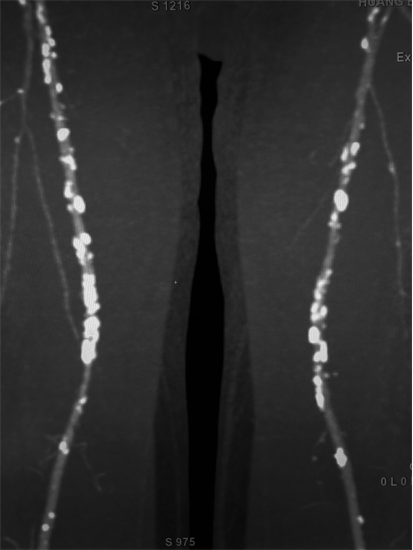

精准评估管腔: 结合多角度造影、定量血管分析(QVA),必要时使用血管内超声(IVUS)或光学相干断层扫描(OCT)来评估夹层、斑块负荷和管腔获得,弥补造影的不足。